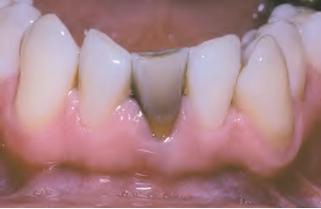

Eruption cyst (EC) | Dentigerous 萌發 | 12a, 12b, 34a, ?6 | 10y ↓ | 藍色或紫棕色 ![]() ![]() |